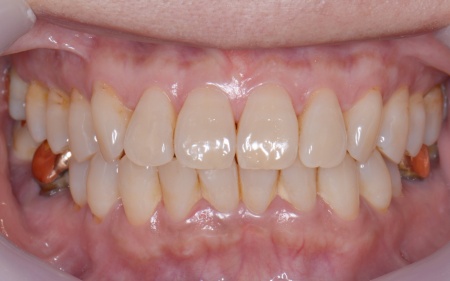

| カウンセリング | 拝見したところ、上下左右の奥歯計8本(第1大臼歯、第2大臼歯)に重度の歯周病が認められました。 歯周病は歯を支えている骨や歯ぐきに炎症が起こる病気です。進行すると歯がぐらついたり、噛む力が弱くなったりします。 さらに悪化すると歯を失う可能性が高くなるだけでなく、周囲の歯にも影響が広がることがあります。 特に下の奥歯2本(左右第1大臼歯)は歯を支えている骨が著しく減少して歯が大きく揺れており、治療して温存することは難しい状態でした。 また、左上の奥歯(第1大臼歯)は過去に詰め物で治療されていましたが、その下で虫歯が再発しています。 以上のことから、下左右の第1大臼歯は抜歯後に歯を補う治療、その他奥歯の治療、再発した虫歯の治療が必要と診断しました。 |

さらに虫歯が再発していた左上奥歯については、虫歯をしっかりと取り除いたうえで被せ物による修復治療を提案しました。 それぞれのメリット・デメリットを丁寧に説明したところ、治療計画に同意いただきました。 まず、歯周基本治療から開始しました。 下左右の第1大臼歯を抜歯し、その部位にインプラントを埋め込む手術を行いました。同時に、インプラントの隣にある下の第2大臼歯に対して歯周組織再生療法を施しています。 また、左上の奥歯は虫歯を取り除いたあと、歯の形を整えて型取りを行い、最終的にジルコニアクラウンを装着しています。 段階的に治療を進め、すべての治療を終了しました。 |